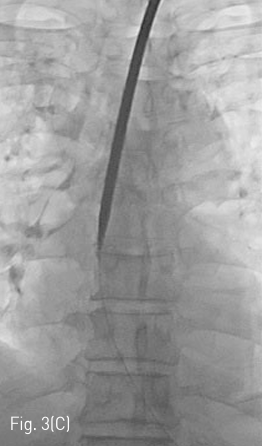

Fluoroscopy 유도하에 경구를 통해 0.035 인치 유도철사 (Glidewire, Terumo, Tokyo, Japan)를 위 속까지 삽입한 후 20mm x 4cm 풍선카테터 (Atlas, BARD, Arizona, USA)를 흉곽입구식도 중간부위에 위치하도록 하였다. 조영제와 생리식염수를 혼합하여 풍선카테터를 팽창시켰고, 초음파 유도하에 팽창된 풍선을 percutaneous transesophageal approach 하여 18게이지 바늘 (Chiba biopsy needle, Cook, Bloomington, USA)로 천자하였다(Fig. 2. A-B). 천자 바늘의 속심을 제거한 후 조영제가 역류되는 것을 확인하였다. J-tip 유도 철사 (J-Tip Glidewire, Terumo, Tokyo, Japan)를 터진 풍선 내로 전진시키고, 터진 풍선과 J-tip 유도철사를 식도하부 혹은 위 안쪽에 위치시킨 후(Fig. 3A) 터진 풍선과 입을 통해 삽입되었던 0.35 인치 유도철사를 제거하고 transesophageal J-tip 유도 철사만 남겨 놓았다. (Fig. 3B) 순차적으로 12Fr, 14Fr dilators (Dilator, Cook, Bloomington, USA)를 이용하여 tract을 확장 시켰다. 18Fr 분리 제거형집(Enteral access dilation system, HALYARD, Alpharetta, USA)을 거치한 뒤 (Fig. 3C) 14Fr 빈천자창냄 카테터(MIC; jejunal feeding tube, HALYARD, Alpharetta, USA)를 십이지장내 세번째 부위까지 진입시키고 분리제거형집을 제거하였다(Fig. 3D). 삽입된 카테터는 목 피부에 봉합하여 고정하고 시술을 종료하였다.

Fig 3C

(C) After gradually increasing size of dilatation via 12Fr and 14Fr dilators, 18Fr peel away sheath is inserted over the J-tip guidewire.